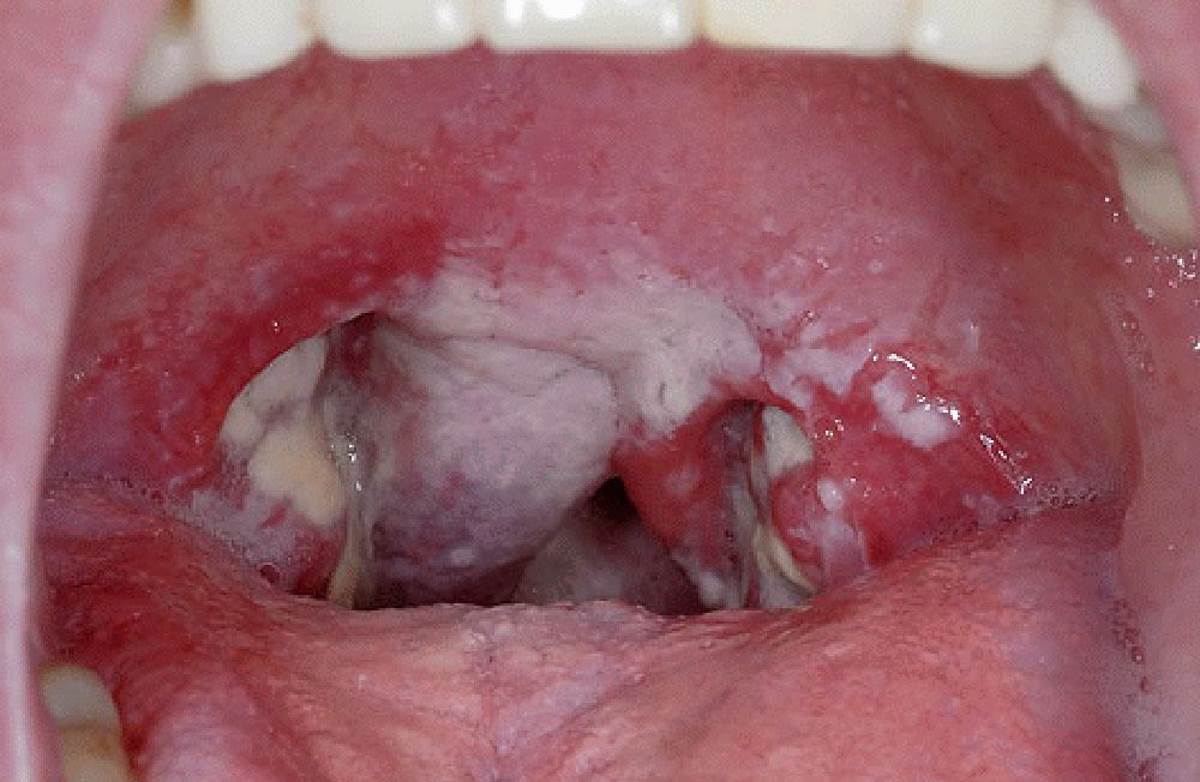

Кандидоз глотки

Полный размер 1200 × 782 пикселей Кандидоз полости рта